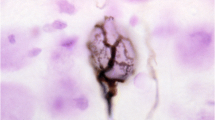

3.1 Abnormal Cochlear Morphology

Degeneration in the inner ear of congenitally deaf white cats was first reported at the turn of the 20th century (Rawitz, 1897; Alexander, 1900; Alexander & Tandler, 1905). Many subsequent observations have described this condition in detail, which is characterized by a collapse of Reissner’s membrane onto the undifferentiated organ of Corti, a thinning of the stria vascularis, and a malformation of the tectorial membrane (Fig. 2; Wolff, 1942; Wilson & Kane, 1959; Bosher & Hallpike, 1965; Mair, 1973; Rebillard et al., 1981a; Ryugo et al., 2003). This pattern of cochlear deterioration is the predominant pathological finding in these animals (Ryugo et al., 2003). Degradation is also present in the saccular partition (Mair, 1973), and the combined cochleosaccular defects closely mirror that of the Scheibe deformity of deaf-mutism reported in humans (Scheibe, 1892). Early observers of this coincidence advocated for the use of animal models such as the deaf cat in research programs studying congenital deafness (Fraser, 1924).

Light micrographs of mid-modiolar, Nissl-stained cochlear sections showing the organ of Corti from normal hearing (left) and congenitally deaf (right) cats. Note the collapsed Reissner’s membrane and absent organ of Corti from the deaf cat. Scale bar = 50 μm. BM, basilar membrane; RM, Reissner’s membrane; SL, spiral limbus; SP, spiral prominence; SV, stria vascularis; TM, tectorial membrane. (Adapted from Ryugo et al., 2003)

Several studies have described the early stages of cochlear degeneration (Bosher & Hallpike, 1965; Mair, 1973; Mair & Elverland, 1977; Rebillard et al., 1981a; Ryugo et al., 2003; Baker et al., 2010). At birth, the cochlear morphology of kittens destined to become deaf is similar to that of pigmented kittens, with inner and outer hair cells intact in both groups (Heid et al., 1998; Baker et al., 2010). At postnatal day 3, ultrastructural abnormalities are apparent in strial cells (Mair & Elverland, 1977). Definite pathological signs begin to emerge by postnatal day 5 (Bosher & Hallpike, 1965; Mair, 1973; Baker et al., 2010): the stria vascularis appears abnormally thin and Reissner’s membrane begins to elongate, causing it to ruffle irregularly along its length. In addition, the tectorial membrane begins to shrink, curling upon itself and rolling against the spiral ligament. The expansion of Reissner’s membrane continues in rapid fashion such that by the end of the second postnatal week it has collapsed completely. At this point, the tectorial membrane is also tightly bound to the spiral ligament. By the start of the third postnatal week the pathology appears complete, with a total absence of the cochlear duct, organ of Corti, and hair cells. The specific genetic and molecular cause(s) of this cochlear degeneration in the white cat remain unknown (Geigy et al., 2007).

The congenital degeneration of the cochlea typically occurs bilaterally, but it is also possible to find instances of unilateral and/or partial malformations accompanied by a hearing impairment rather than a profound loss (Mair, 1973; Rebillard et al., 1981a; Ryugo et al., 1998). Early reports suggested that cochlear degeneration is an all-or-nothing phenomenon (Bosher & Hallpike, 1965; Bergsma & Brown, 1971; Mair, 1973), but later research demonstrated that differing degrees of pathological severity are possible, and that the degenerative process is not necessarily continuous with age (Rebillard et al., 1981a; Ryugo et al., 2003).

A second, less common type of cochlear pathology has also been identified in congenitally deaf white cats (Ryugo et al., 2003). This pattern takes the form of excessive growth of epithelial cells on Reissner’s membrane and within the membraneous labyrinth. This hypertrophic growth effectively smothers the organ of Corti and stria vascularis, causing Reissner’s membrane to completely fill the space of the cochlear duct. Unlike the degenerative collapse described previously, this abnormal growth may manifest at or before birth (Baker et al., 2010). Less frequently, a combination of both exuberant growth at the apex and collapse of Reissner’s membrane at the base of the cochlea has been observed (Ryugo et al., 2003). All aforementioned types of cochlear pathologies, however, result in sensorineural deafness.